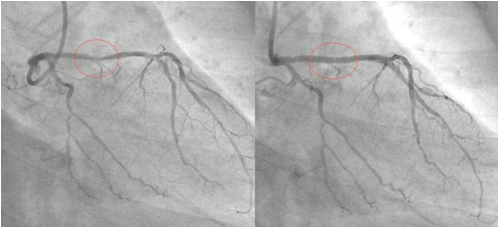

这位Hakim让他自己在家中做一个食疗,他吃了一个月。一个月后他去同一家医院做检查,发现三条血管干干净净,原来堵塞的地方已经全通了。他是一位虔诚 的回教徒,为了让更多的人受益,他把自己的经验放在网上分享,他的前后两张血管照片也放了在网上,在 照片中,服用食疗之前与之后的分别连普通人也看得出来。